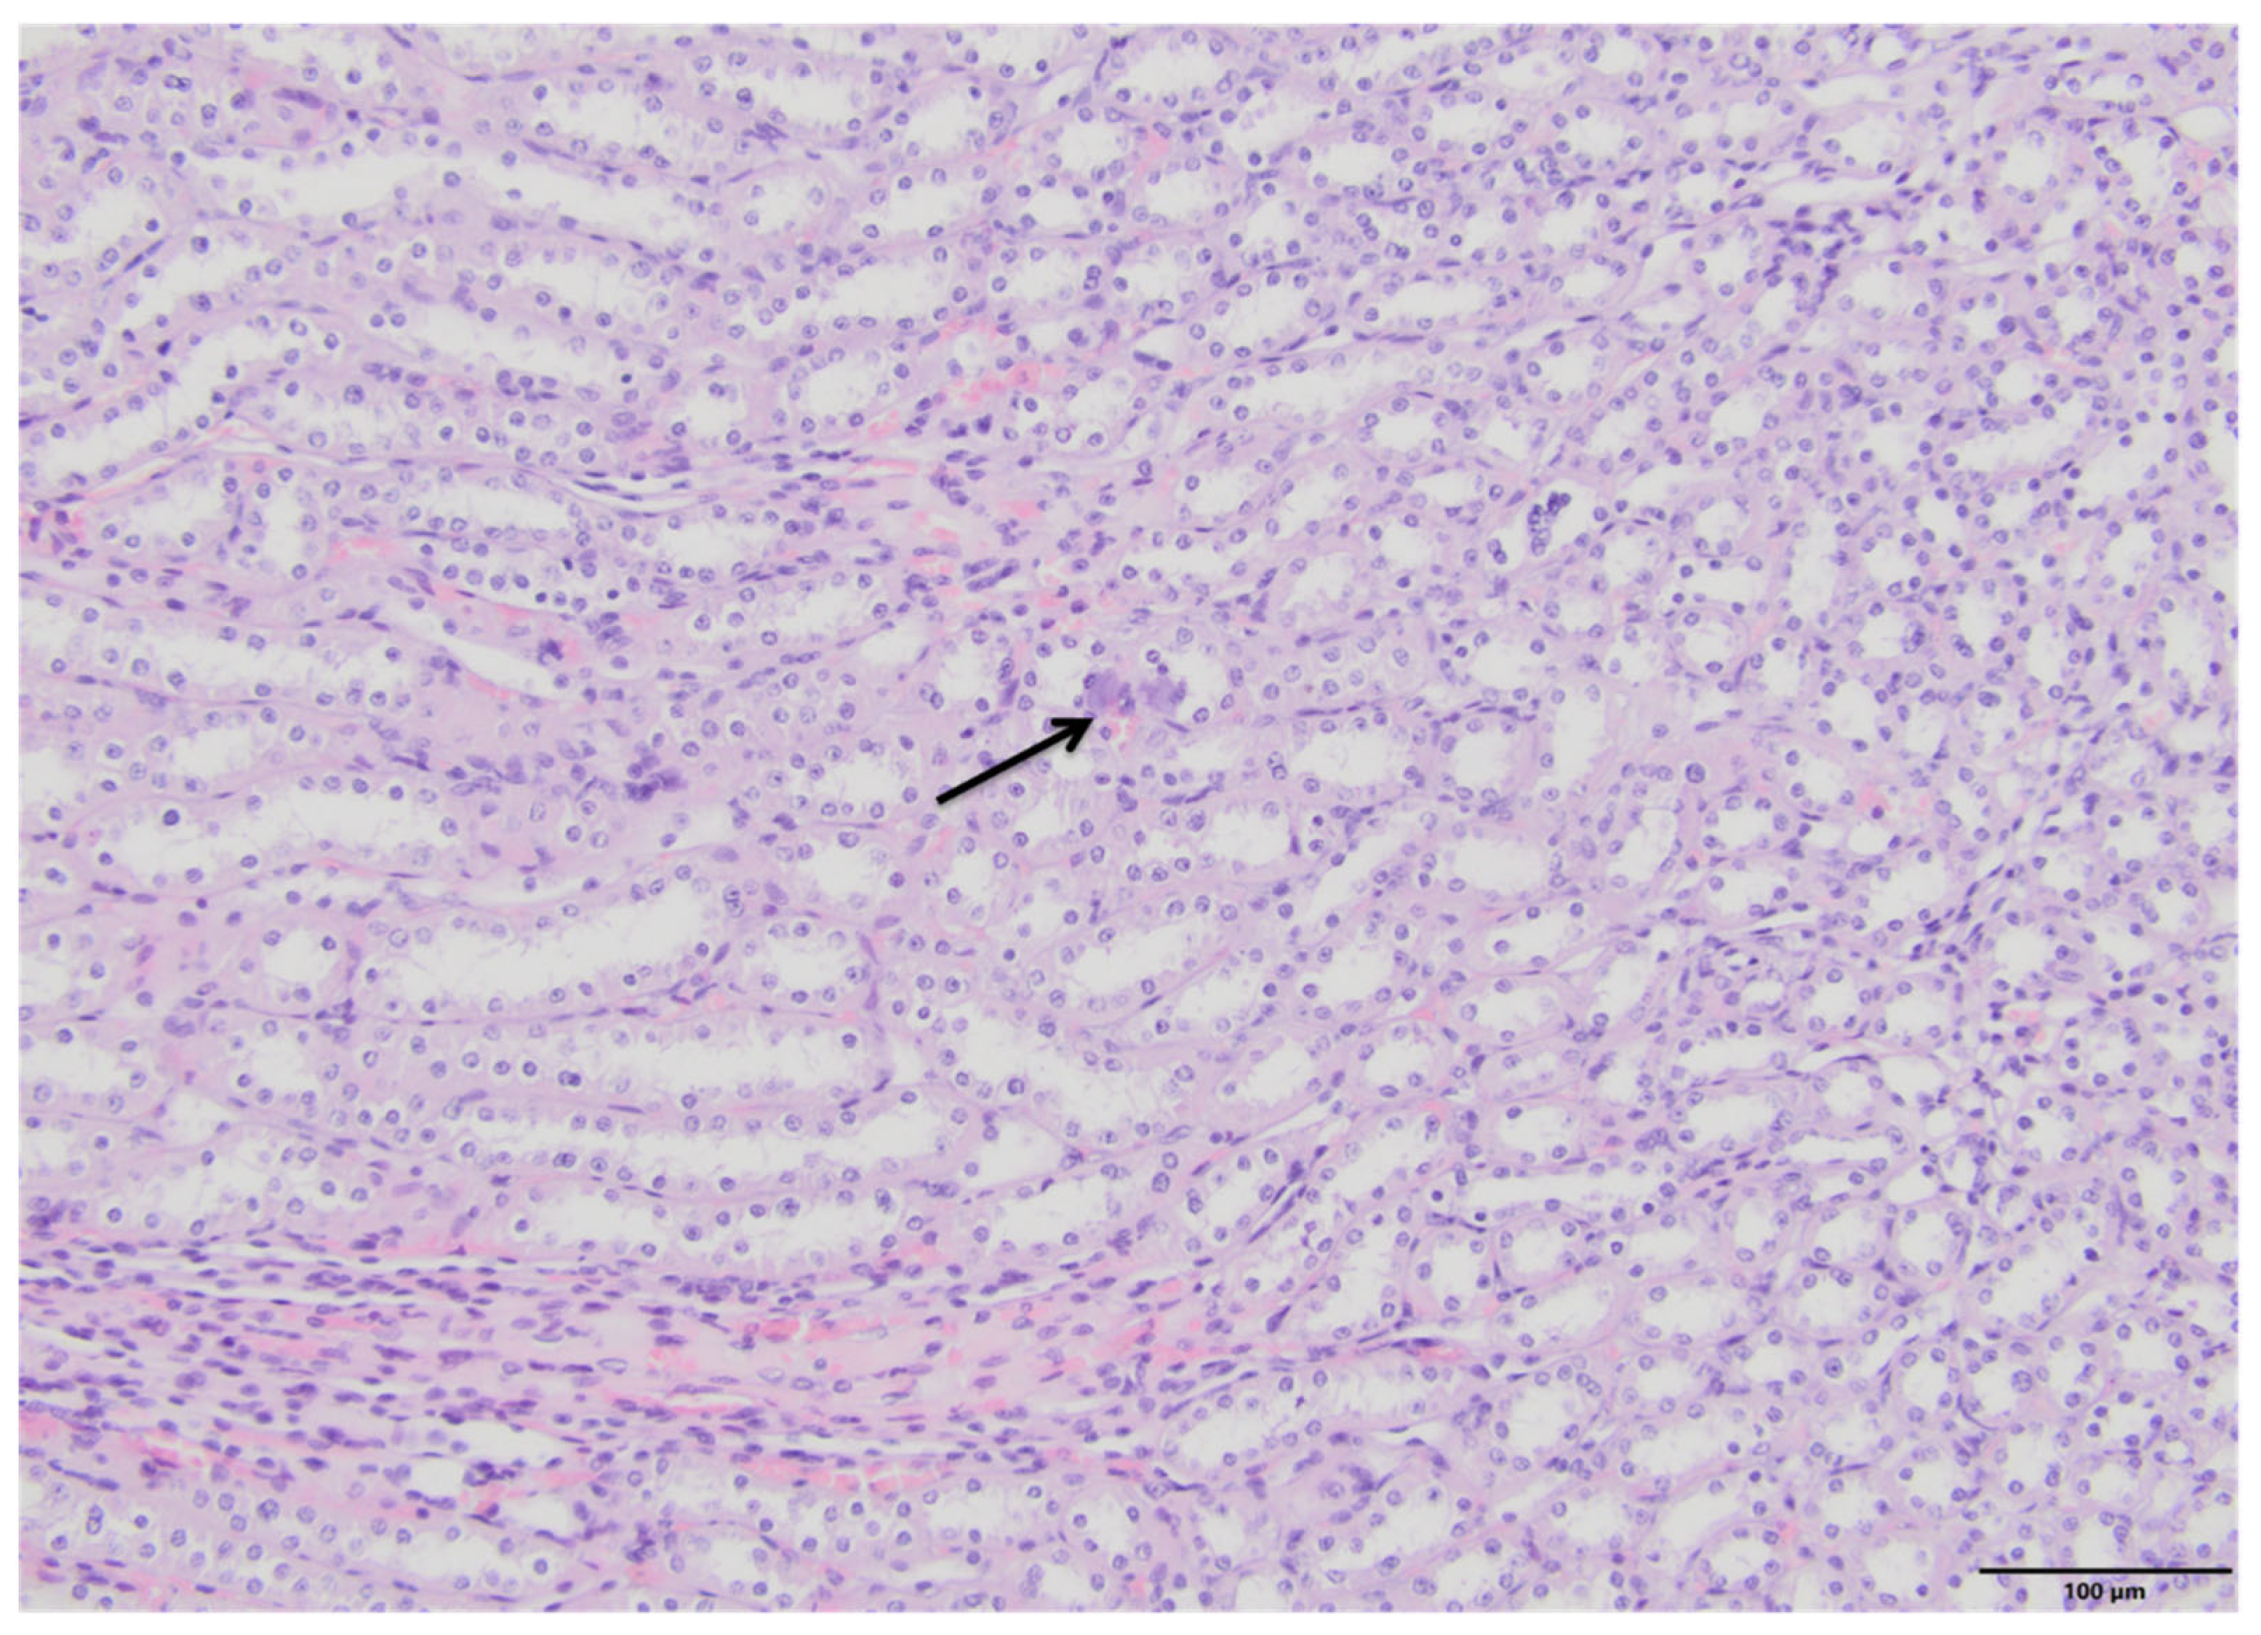

2.4. Kidney Histopathology